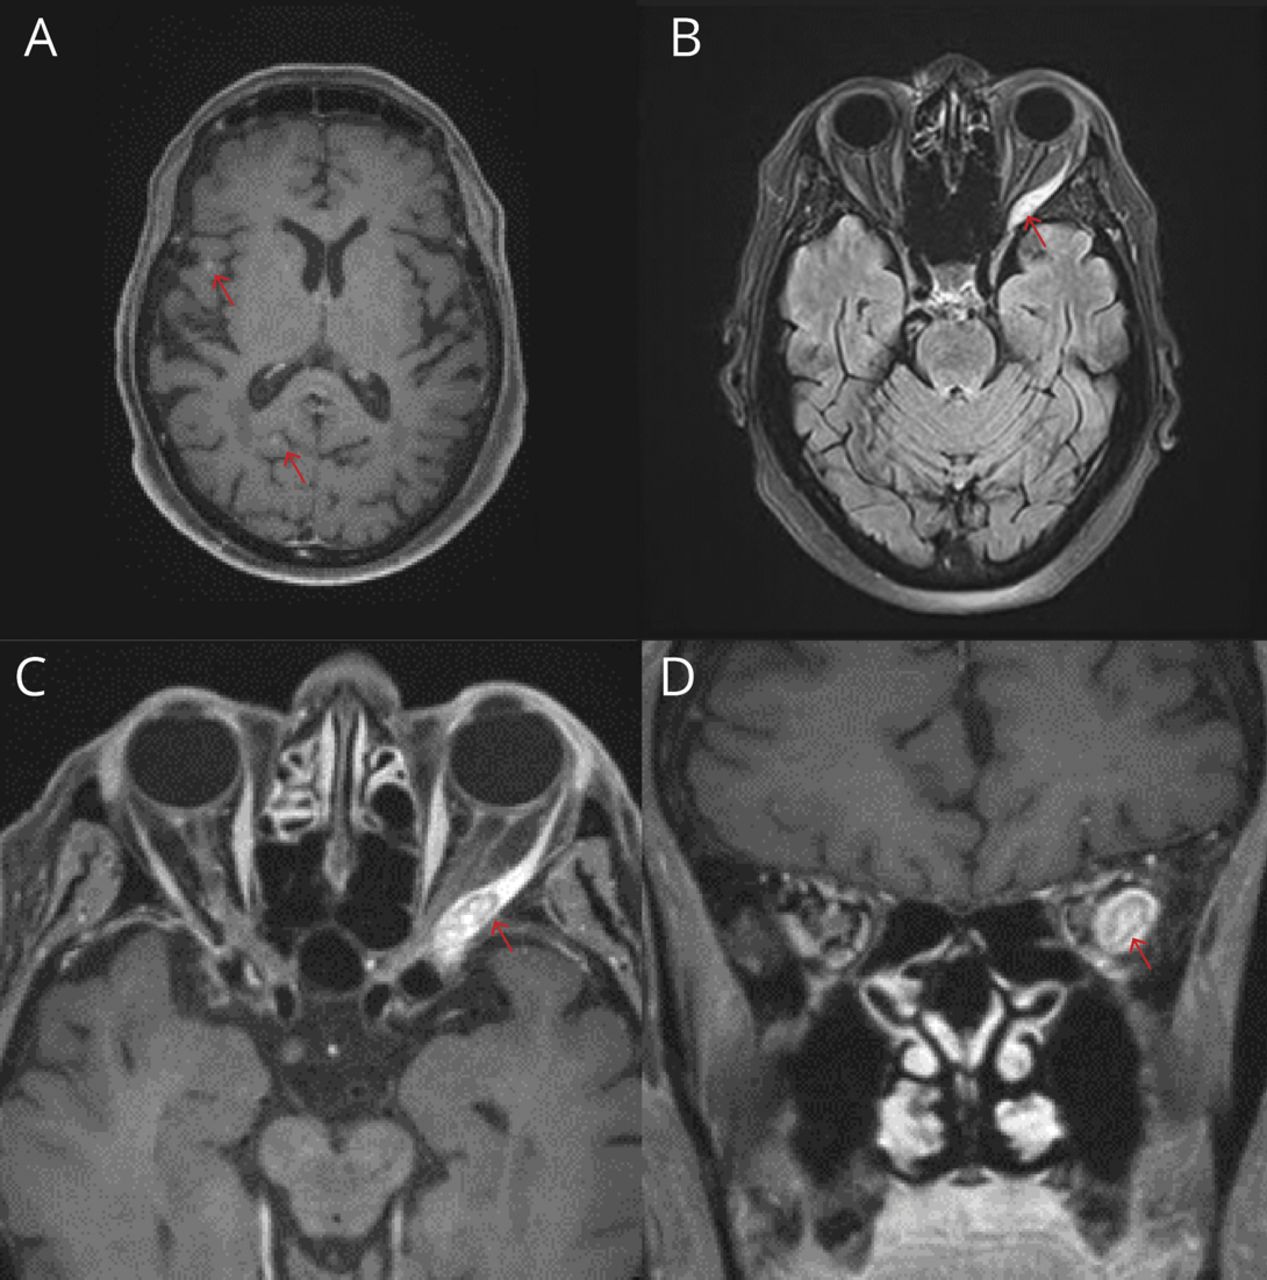

一位80岁的女性,先前切除了右大腿黑素瘤,出现急性双眼复视。神经学检查显示左眼不能外展,右眼内收正常。其他检查正常。左外侧直肌麻痹可由缺血性、炎症、自身免疫、压迫或肿瘤病因引起。MRI轨道发现了一个与眼外肌转移一致的增强的左外侧直肌病变。脑部核磁共振显示多处亚厘米强化病灶(数字).1随后的淋巴结活检证实是转移性黑色素瘤。尽管进行了放疗和bfraf靶向全身治疗,患者病情迅速恶化,并在初始评估后5个月死亡。2

大脑和轨道的核磁共振成像

(A) t1加权MRI轴向对比后显示亚厘米右额部和右枕部强化病灶与转移一致(箭头)。(B) t2加权液体衰减反转恢复MRI显示左外侧直肌病变(箭头)。(C)眶侧t1加权MRI增强后,轴向视图显示累及左外侧直肌的病变增强(箭头)。(D)眶侧t1加权MRI增强后,冠状面显示病变增强,累及左外侧直肌(箭头)。